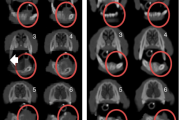

Crohni tõbi